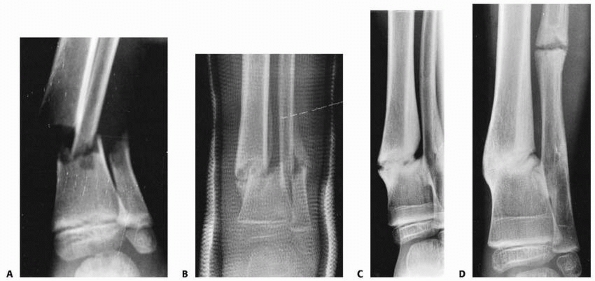

should be obtained whenever a tibial and/or fibular shaft fracture

is/are suspected. While uncommon, tibial shaft fractures may occur in

combination with transitional fractures involving the distal tibial

metaphysis, and as such, close evaluation of the ankle radiographs is

essential (Fig 25-17A-D). Comparison views of the uninvolved leg normally are not indicated. Children with suspected fractures not

FIGURE 25-17 A. Anteroposterior radiograph of an adolescent patient with a tibial shaft fracture. B-D. Anteroposterior, lateral, and mortise views of the ankle demonstrate an associated triplane fracture.